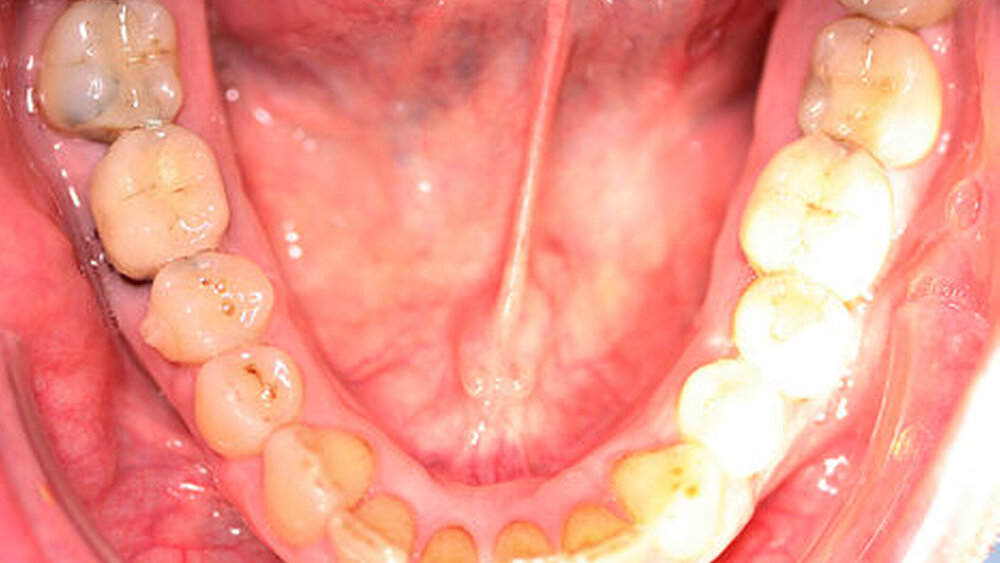

Röntgenologisch stellte sich im Orthopantomogramm der bereits intraoral ersichtliche horizontale und vertikale Knochenabbau mit Attachmentverlust an einzelnen Zähnen dar. Die Erhaltungswürdigkeit einzelner Zähne war aufgrund des starken Knochenverlustes beziehungsweise der Beeinträchtigung des Halteapparates als kritisch zu beurteilen.

Zudem wurde die Diagnose einer Parodontitis gestellt, die eine Rücküberweisung an den Hauszahnarzt erforderlich machte (Abbildung 2).